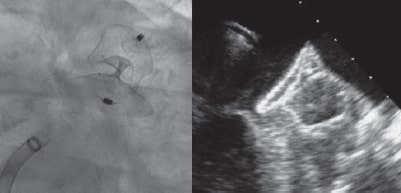

La intervención se llevó a cabo con un dispositivo Amulet de 28 mm. Se avanzó una vaina introductora de 14 Fr por vía transeptal a la aurícula izquierda y, tras una angiografía selectiva, se implantó el dispositivo dentro de la orejuela de forma habitual. Como el dispositivo no se colocó bien la primera vez (parcialmente fuera de la orejuela) hubo que recapturarlo. En el segundo intento y con una importante rotación de la vaina en sentido antihorario, el cuerpo del dispositivo quedó colocado con un peculiar «retorcimiento» (figura 2) con el extremo distal dentro de la orejuela. Se recapturó con cuidado y, tras descartar derrame pericárdico, se reimplantó, esta vez correctamente, sin ser necesario cambiar el dispositivo (figura 3). La ecocardiografía transtorácica realizada al día siguiente descartó la presencia de derrame pericárdico. La ETE que se realizó al cabo de 1 mes descartó la presencia de fugas o trombos en el dispositivo.

Figura 3.